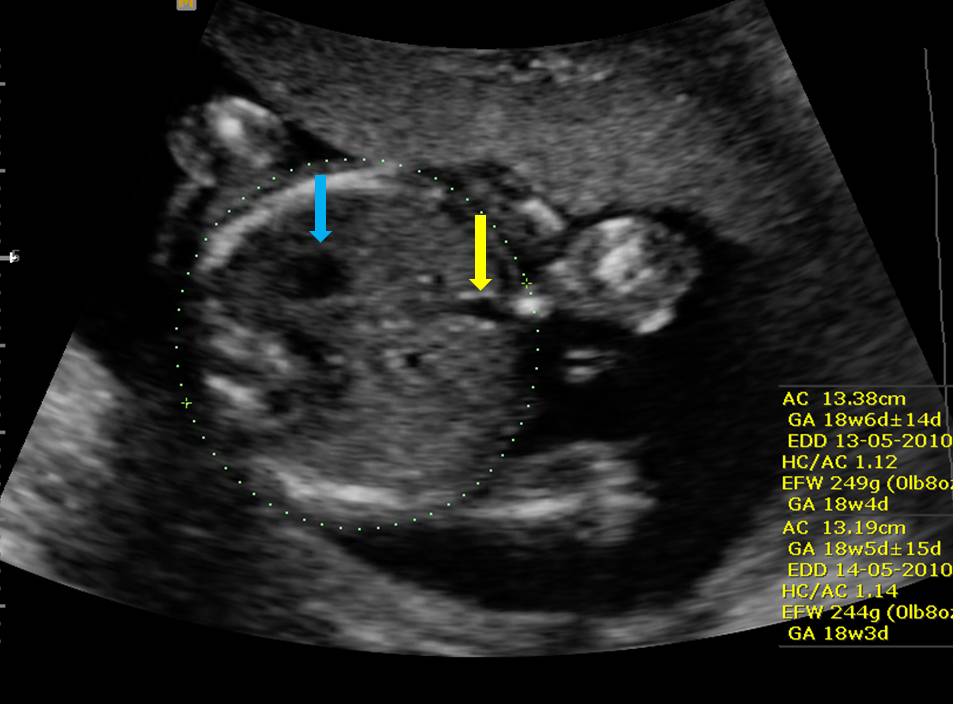

Fetal abdominal sonogram for measurement of abdominal circumference Why Is Abdominal Circumference Small fetuses with isolated abdominal circumference <10% are at increased risk of perinatal complications. formal ultrasonography is the standard for diagnosing fetal growth restriction if estimated fetal weight or abdominal circumference is below the 10th percentile. — his abdomen has been smaller than the rest of him the whole time, but it was never worrisome. these findings. Why Is Abdominal Circumference Small.

Abdominal Circumference Why Is Abdominal Circumference Small we recently determined that small abdominal circumference (ac) is highly correlated with small for gestational age. abdominal circumference is a measurement taken in the transverse plane at the fetal liver to determine proportionality with the. these findings suggest that the label of small abdominal circumference in fetuses with a normal estimated weight might. formal ultrasonography is. Why Is Abdominal Circumference Small.